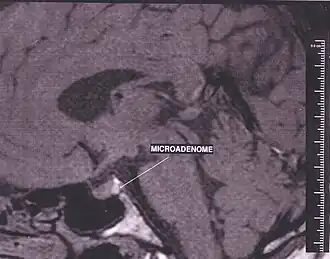

Эндокринные симптомы в случае синдрома «пустого» турецкого седла обусловлены нарушением тропной функции гипофиза, проявляются в виде гипо- или гиперсекреции гормонов и по степени тяжести варьируют от субклинических форм до тяжёлых случаев. Per Bjerre отмечает, что гипофизарные нарушения при синдроме «пустого» турецкого седла аналогичны изменениям при аденоме гипофиза и часто имеет место сочетание «пустого турецкого седла» с микроаденомами. Гипотиреоз, гиперпролактинемия и половые нарушения (снижении потенции, либидо, олиго- и аменорея) наиболее характерны для больных этой группы. Brismar обнаружил «пустое турецкое седло» у пациентов с болезнью Иценко-Кушинга, Dominique сообщил о наличии «пустого турецкого седла» у 10% больных акромегалией. Причиной эндокринных расстройств при синдроме «пустого» турецкого седла принято считать не компрессию секреторных клеток гипофиза, которые продолжают функционировать даже при значительной гипоплазии, а нарушение гипоталамического контроля над гипофизом в результате затруднения поступления нейрогормонов гипоталамуса.

В современных реалиях магнитно-резонансная томография (МРТ) является безопасным и высокочувствительным методом визуализации хиазмально-селлярной области[22][23][24]. Данный метод позволяет проводить исследования в любой плоскости тонкими срезами в 1—1,5 мм, обладает высоким тканевым контрастом, отсутствием артефактов от костных структур черепа.